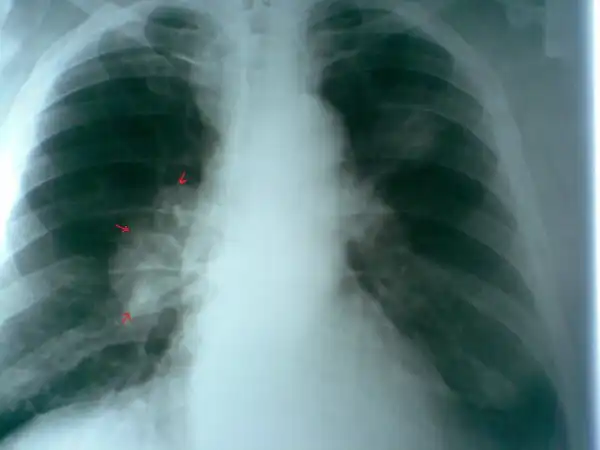

Пациент № 1:

2. По поводу снимков... Сомнение вызывает первый пациент. 2 фокуса в разных легких... Разве что метастазы в прикорневые л\у правого легкого... Да и контуры очень четкие в левом легком... Верхняя доля... Дорожка к корню... Больше похоже на туберкулез ИМХО. Хотя и лучистость есть... Спорно.

Пациенты 6 и 7 тоже под вопросом... Не четкая картина.